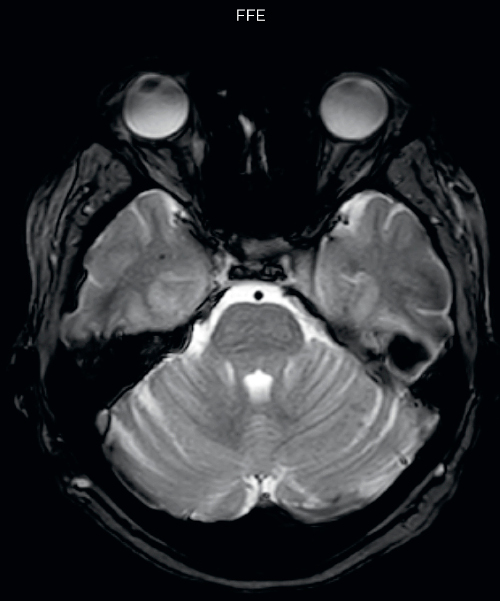

Hemosiderin foci in brain

Gradient echo imaging and SWIp are compared in a patient with radiation-induced foci of hemosiderin deposition. A greater number of small foci is seen on the SWIp image. Ingenia 3.0T

UVM case 1 FFE hemosiderin foci in brain1

UVM case 1 SWIp hemosiderin foci in brain1